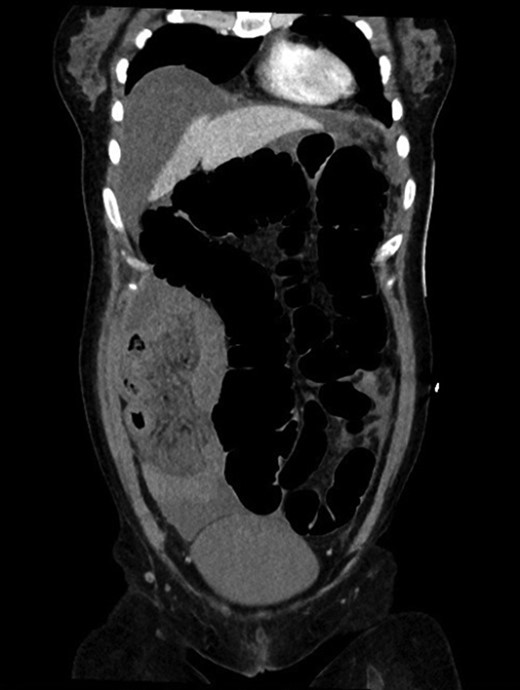

Colonoscopy revealed melanosis coli, diverticulosis and grade four hemorrhoids. She was admitted overnight following haemorrhoidectomy. The following morning she complained of abdominal pain, which she described similar to diverticulitis, and she was tender on exam. To rule out perforation, a plain film abdomen was performed. Findings were suggestive of gaseous distension following colonoscopic air insufflation without evidence of free gas (Fig. 1). Watchful waiting approach was adopted, however the patient deteriorated further during the course of the day. She had a vasovagal episode with tachycardia (134 bpm) and hypotension (67/47 mmHg). A venous blood gas revealed lactate level of 7 mmol/l. She underwent an urgent CT with findings suggestive of pericaecal internal hernia with the ileal loops located in the right paracolic gutter demonstrating features of ischemia (Fig. 2). There was moderate amount of free fluid, but no free gas to suggest perforation (Fig. 3). She was taken to theater that day for emergency laparotomy. The intraoperative findings included two litres of bloodstained fluid and floppy cecum with a band of adhesion to its own mesenteric base, probably adhesional having developed after the appendicectomy. This band has created a window through which three quarters of her small bowel had herniated and became strangulated. The bowel looked very ischemic, but not necrosed. The surgeons divided the adhesion, untwisted the small bowel and waited 20 minutes to allow sufficient time for bowel ischemia to recover. Fortunately, she did not require any bowel resection.

CT axial view showing dilated colon, internal hernia with ischemic small bowel loops, free fluid, but no free gas.